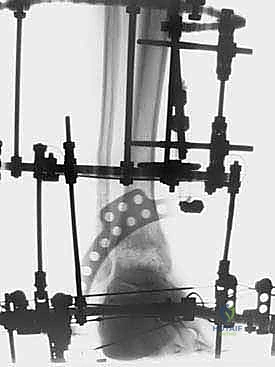

الخطوة الثانية: تركيب الإطار الخارجي (Ilizarov Frame)

هذه هي المرحلة الهندسية الدقيقة. يتم تركيب حلقتين معدنيتين حول عظمة الساق (Tibia) وحلقة ثالثة حول القدم (تثبت في عظمة العقب Talus وعظام مشط القدم).

الخطوة الثالثة: إدخال الأسلاك والمسامير (Wire and Pin Placement)

يتم تمرير أسلاك معدنية رفيعة جداً (Kirschner wires) ومسامير نصفية (Half-pins) عبر العظام لتثبيت الحلقات. يعتمد الأستاذ الدكتور محمد هطيف على معرفته التشريحية العميقة واستخدام جهاز الأشعة المرئي (C-arm) لضمان مرور هذه الأسلاك في "الممرات الآمنة" (Safe corridors) بعيداً عن الشرايين والأعصاب الحيوية.

الخطوة الرابعة: تركيب المفاصل الصناعية (Hinges)

هنا يكمن السر الأكبر للنجاح. يتم توصيل حلقة الساق بحلقة القدم باستخدام مفاصل معدنية قابلة للحركة (Hinges). يجب أن يتم وضع محور هذه المفاصل المعدنية ليتطابق تماماً مع المحور التشريحي الطبيعي لدوران مفصل الكاحل (Center of Rotation of the Talus). هذه الدقة تضمن إمكانية تحريك الكاحل أثناء فترة العلاج دون إحداث ضغط غير متساوٍ على الغضروف.

الخطوة الخامسة: تطبيق التشتيت (Distraction)

أثناء العملية، يقوم الدكتور هطيف بإبعاد حلقة الساق عن حلقة القدم تدريجياً وببطء باستخدام قضبان ملولبة، حتى يصل إلى مسافة تشتيت تبلغ حوالي 5 إلى 6 ملليمترات. يتم التأكد من هذه المسافة عبر الأشعة السينية داخل غرفة العمليات.

فترة العلاج والتأهيل: 12 أسبوعاً من إعادة البناء البيولوجي

1. المشي وتحميل الوزن (Weight Bearing)

على عكس ما قد يظنه البعض، فإن الراحة التامة في السرير ليست مطلوبة. بل على العكس! يشجع الدكتور هطيف مرضاه على بدء المشي وتحميل الوزن الكامل على الطرف المصاب بمجرد أن يسمح الألم بذلك (غالباً خلال الأيام الأولى).